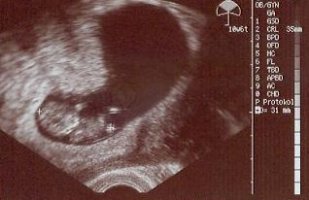

Ich komm grad von Frau Doktor und alles ist prima. Krümel ist wieder einen Zentimeter gewachsen (SSL 3,5 cm) und ist grade aufgewacht. Hat sich gereckt und gestreckt und umgedreht :love1

die Blutungen sind besser geworden und wenn sie nicht wieder mehr werden, muss ich erst in 4 Wochen wieder hin. Ein gutes Zeichen, auch wenn es natürlich viel beruhigender ist, jede Woche zu wissen, ob alles gut ist.